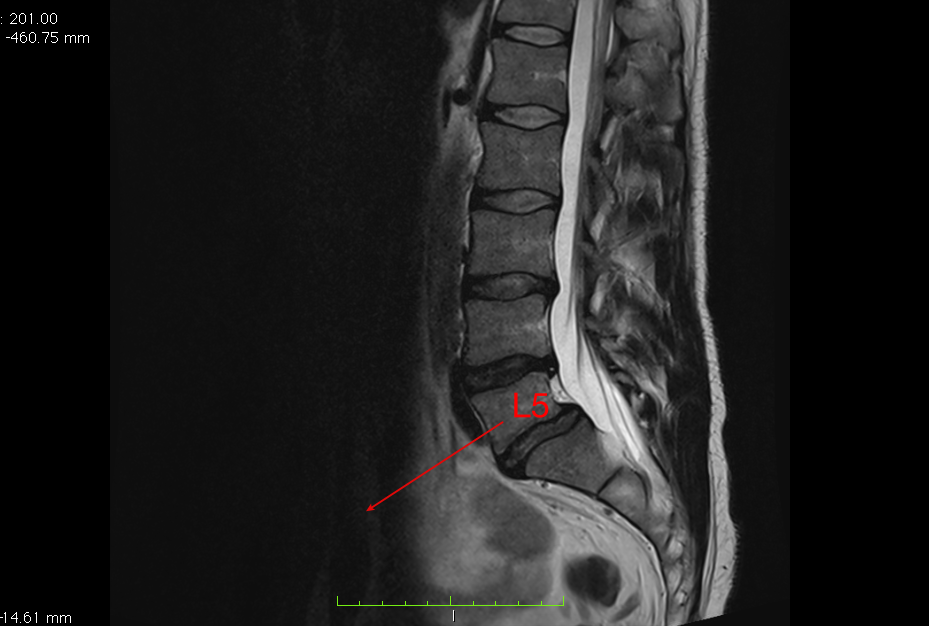

Przodozmyk kręgu L5 spowodowany między innymi zaburzeniami kończyn dolnych oraz innych odcinków kręgosłupa.